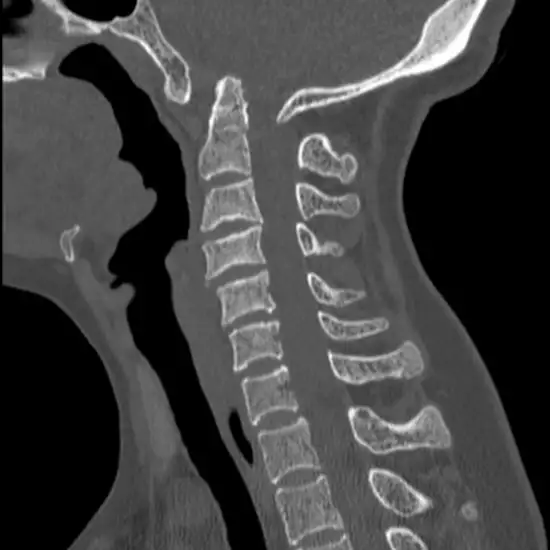

The CV Junction (craniovertebral junction) connects the cranium to the spine. CV Junction is essential for the body's flexibility and stability. CT CV Junction 3D Reconstruction is an imaging scan that produces 3-D images of the craniovertebral junction. CT CV Junction is recommended for diagnosing development variations, malformation, and abnormal motion.

It is an imaging technique that creates cross-sectional images of the cranio-vertebral junction using a rotating beam of X-rays.

CT CV Junction 3D Reconstruction is used to diagnose craniovertebral junction development variations, malformations, and abnormal motion.